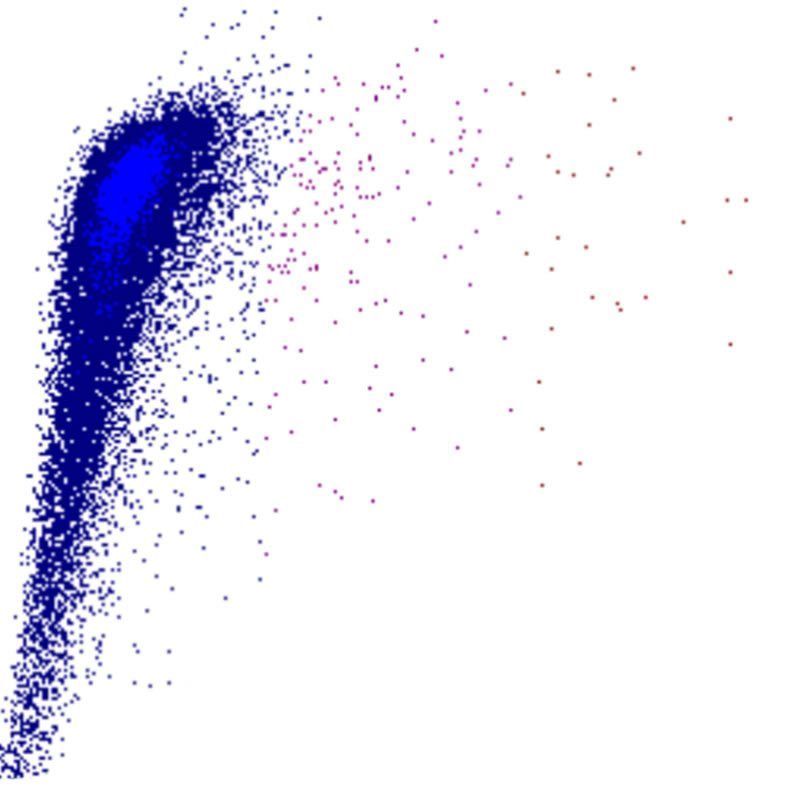

Densité

La densité des points dans un diagramme de dispersion reflète le nombre de cellules présentant des caractéristiques physiques et de fluorescence similaires. Le diagramme indique ainsi non seulement la présence de populations cellulaires, mais aussi leur taille relative et leur homogénéité.

• Une forte densité de points indique une population cellulaire importante et relativement homogène

• Des motifs diffus ou dispersés peuvent suggérer une hétérogénéité, une activation ou la présence de cellules anormales

• Des déplacements, un élargissement ou un chevauchement entre populations constituent souvent des signes précoces de morphologie anormale ou de cellules rares